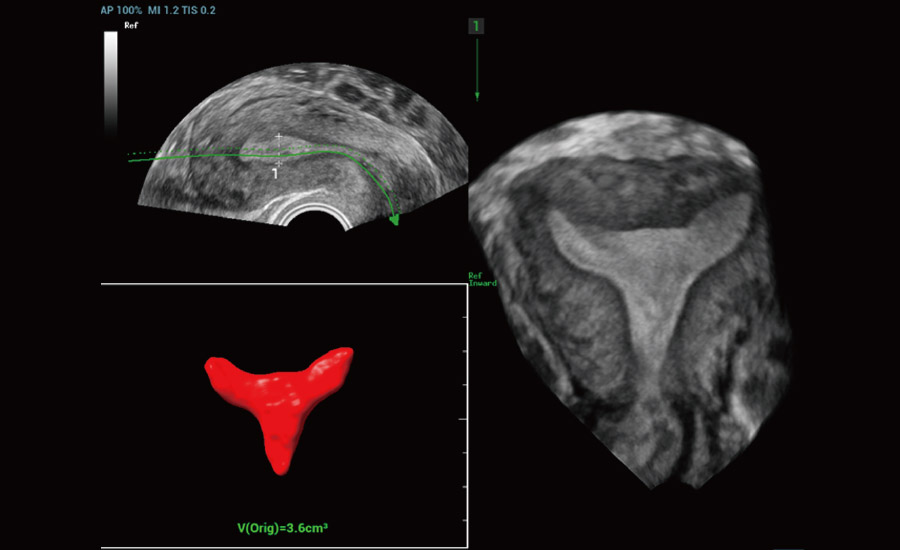

Combining advanced algorithms and domain-specific knowledge, the innovative Smart Scene solution enables auto identification of tissue characteristics and provides organ-specific diagnosis with full-stack intelligence. Based on auto scenario identification, the solution not only realizes smart 2D scanning with auto settings and measurements, but also delivers 3D full-stack intelligence in every step from volume imaging optimization to the difficult 2D plane acquisition, and quantification throughout whole procedure. It helps a lot in reducing the dependency on clinical skills, while increasing diagnostic accuracy, confidence and efficiency.

- Caring for women's health with gynecology and urogynecology solutions

Gynecology

Urogynecology